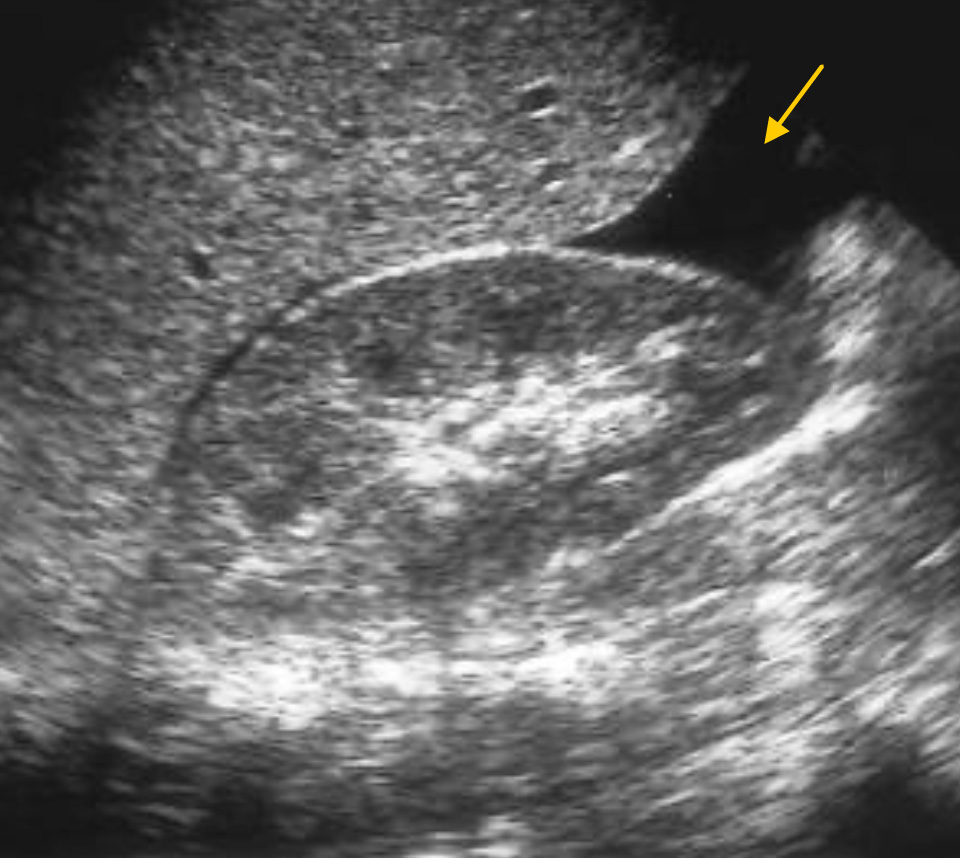

Медицина и диагностика: Инвазивный пузырный занос на УЗИ

Раздел: Альбом идей